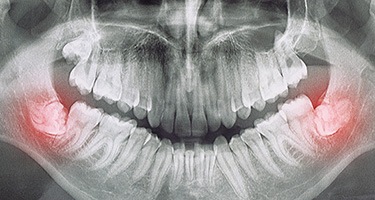

When the wisdom teeth become stuck, or impacted, this can create a variety of unpleasant symptoms, including pain towards the back of the mouth, shifting teeth, a flap in the gums that traps food, and even an infection. Typically, the best way to stop these issues and prevent others from developing in the future is to simply remove these teeth. The procedure usually takes just one or two appointments depending on the number of teeth, and the recovery time is often less than a week.

The very first step is always the same: numbing your mouth. That way, you don’t feel any pain during your time in the treatment chair. Once you’re ready to begin, our talented and experienced emergency dentist will gently grip the tooth, rock it loose, and extract it. Unless, of course, the wisdom tooth that needs to be removed is trapped underneath your gumline. In that case, Dr. Oshins will need to make an incision in your gums first to access it. Then, he will remove it piece by piece, helping to preserve your jawbone in the process.

If your wisdom teeth aren’t causing you any pain, but they do increase your risk of serious oral health problems, like infections and cysts, you should have them removed. If you have any questions about your treatment, including why your dentist recommends it, don’t hesitate to ask! They can review your X-rays, share their reasoning, and let you know what could happen if you don’t get the care you need now. That way, you feel completely confident moving forward.